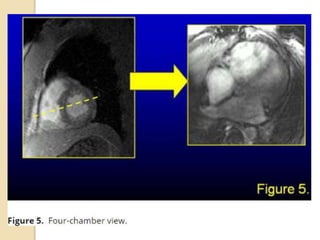

4 chamber view

 The horizontal long axis(4 chamber

view) is generated by selecting the

horizontal plane that is perpendicular

to the short axis

4 chamber view The horizontal long axis(4 chamber view) is generated by selecting the horizontal plane that is perpendicular to the short axis